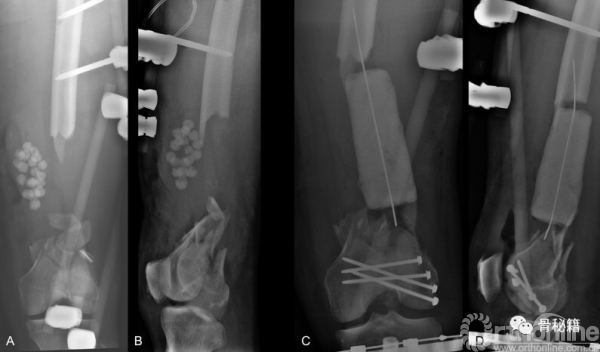

首先,感染控制住了,更换了内固定+磁力髓内钉+一组滑轮

由于远端大量骨缺损,先行了Liss钢板固定远端

同时给与近端股骨磁力髓内钉,同时进行截骨

滑轮是将截骨近端和远端锁定进行了一个套索,但是远端选择了游离

按照此路径进行了骨延长后,可见骨的生长,截骨块已经延长了一部分